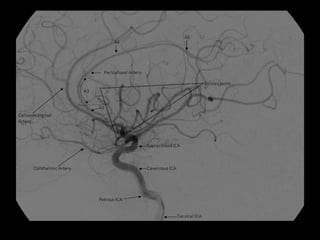

-3D frontal view following left

vertebral artery injection , shows

the intracranial vertebral basilar

circulation in a patient with

severe atherosclerotic vascular

disease , note the moderately

severe stenosis of the midbasilar

artery in addition to a generalized

vessel irregularity

1 vertebral artery

2 (PICA)

3 basilar artery

4 (AICA)

5 (SCA)

5v vermian branch of SCA

5h hemispheric branch of SCA

6.1 P1 segment of (PCA)

6.2 P2 segment of (PCA)

8 posterior temporal branch of

PCA

9 parieto-occipital branch of PCA

10 calcarine branch of PCA